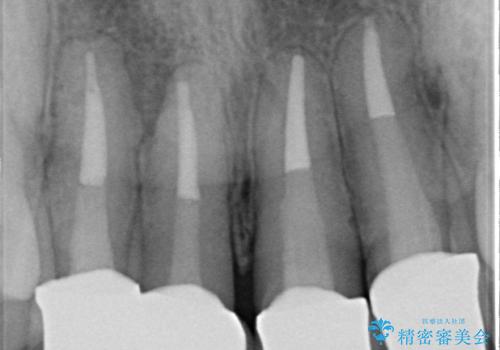

- 20年前に治療した前歯のセラミッククラウンが老朽化し見た目の改善を求めて来院されました。

不十分な根管治療を含めたセラミッククラウンのやりかえ治療を計画します。